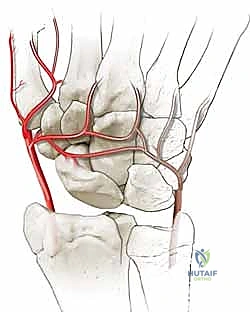

Crucially, the scaphoid's vascular anatomy plays a definitive role in its propensity for nonunion and dictates our surgical approaches. Taleisnik and Kelly meticulously described the intraosseous blood supply, highlighting its retrograde nature. The primary vascular contributors are the laterovolar and dorsal vessels.

Figure 2B: Dorsal intraosseous blood supply to the scaphoid, which enters via the dorsal ridge and supplies the proximal pole.

Navigating the neurovascular structures requires vigilance. The radial artery courses dorsally and radially through the anatomic snuffbox, giving off the dorsal carpal branch which supplies the dorsal scaphoid ridge. During a dorsal approach, this artery and its branches must be mobilized and protected. The superficial sensory branch of the radial nerve (SRN) crosses the surgical field superficially. It is highly susceptible to traction injury or iatrogenic transection, which can result in a debilitating, painful neuroma that often overshadows the benefits of the bony procedure. On the volar aspect, the Flexor Carpi Radialis (FCR) tendon serves as our primary surgical landmark. The FCR tendon sheath is incised, and the tendon is retracted ulnarly to expose the deep volar capsule. The median nerve lies ulnar to the FCR and is generally safely out of the operative field, provided retractors are placed judiciously.